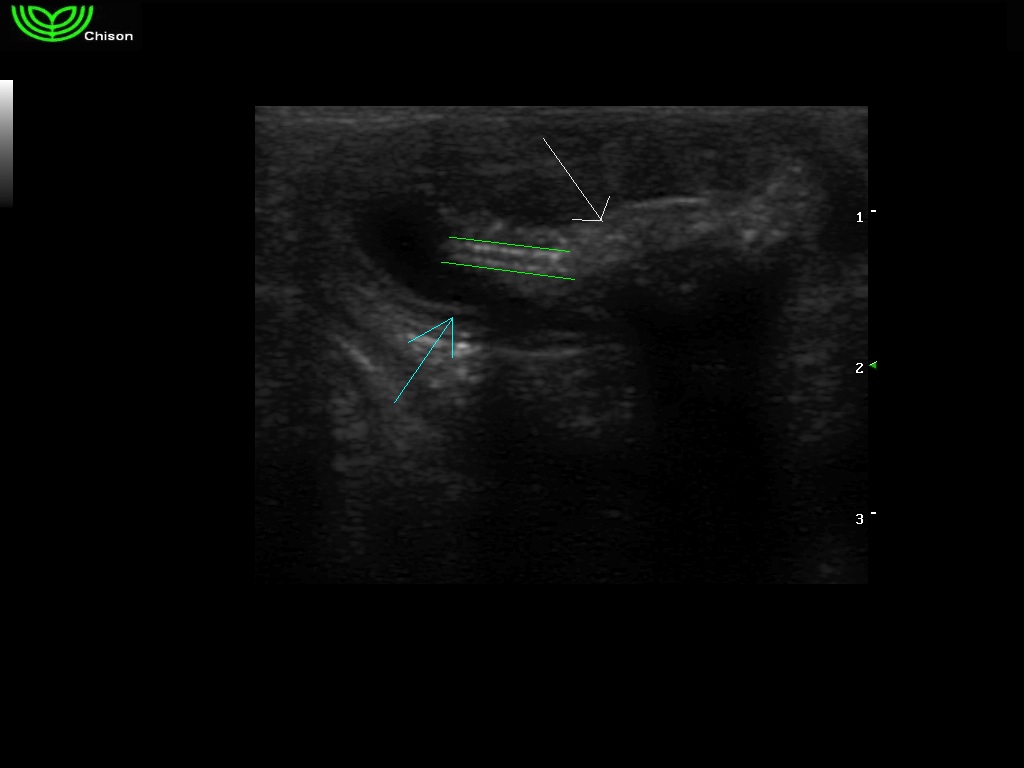

μπλέ βέλος τοίχωμα λεπτού εντέρου, ανάμεσα στις πράσινες γραμμές βρίσκεται το σχοινί ( δύο παράλληλες άσπρες γραμμές), άσπρο βέλος εντερικό περιεχόμενο.